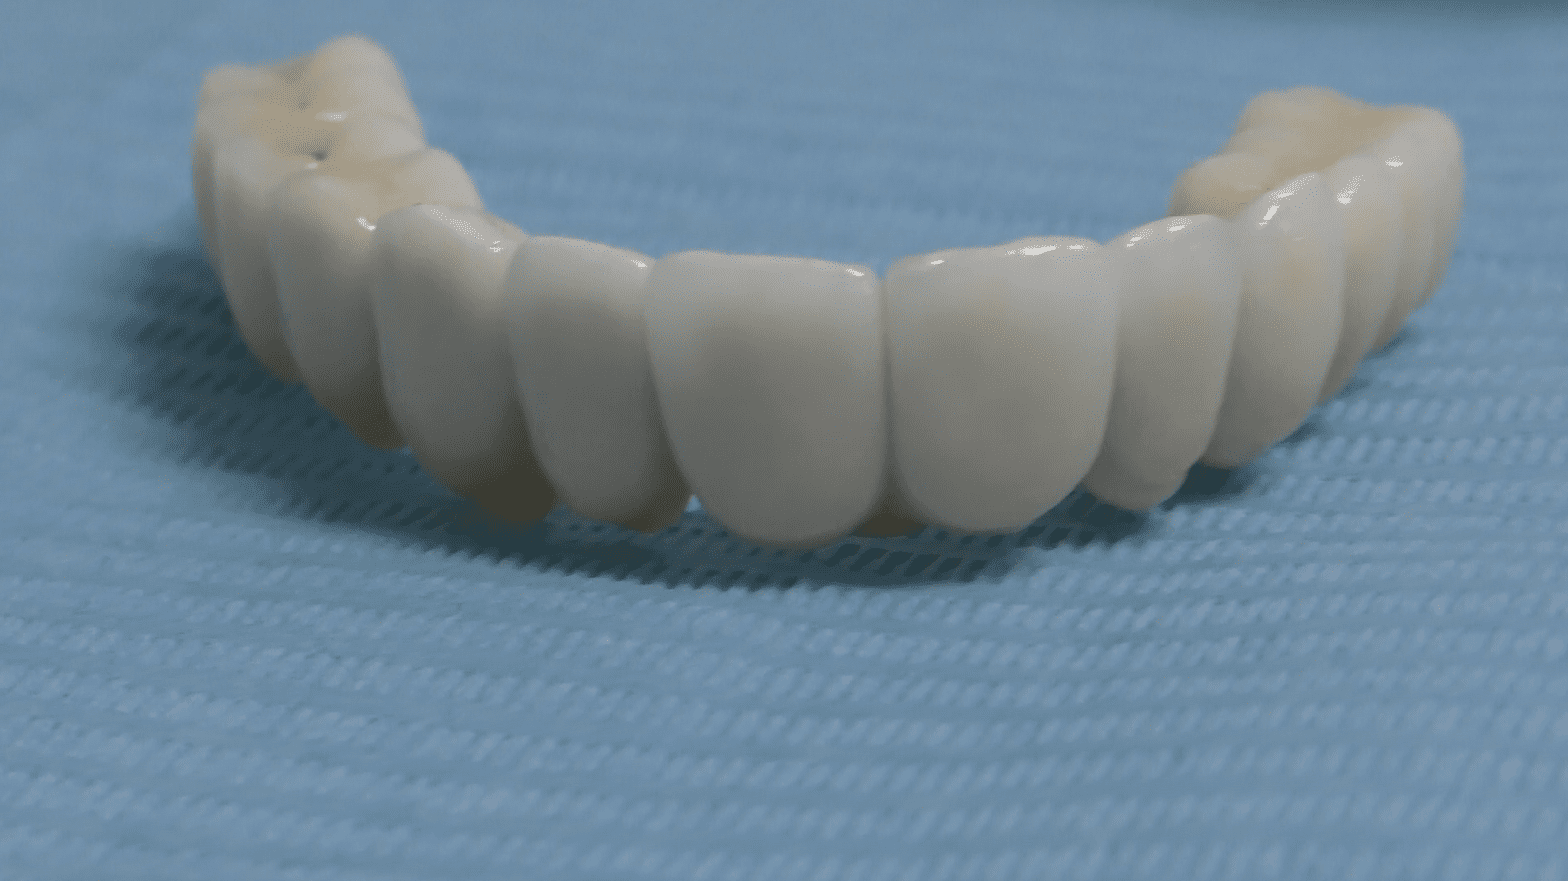

Protesi Circolare: Un Capolavoro Artigianale

Le nostre protesi circolari senza gengiva sono un capolavoro artigianale, realizzato su misura per ogni paziente. La forma circolare della protesi è studiata per adattarsi armoniosamente alla tua bocca, distribuendo uniformemente la pressione masticatoria e garantendo comfort e stabilità.

• Ceramica o Zirconia:

• Le nostre protesi sono realizzate con materiali di alta qualità, come la ceramica o la zirconia, garantendo una resa estetica straordinaria e una durata nel tempo senza eguali.

• Senza Falsa Gengiva:

• La nostra firma è la protesi circolare senza falsa gengiva. Eliminiamo i confini artificiali per un sorriso che sembra naturale e autentico.

• 12/14 Denti su Misura:

• Personalizziamo ogni protesi in base alle tue esigenze, offrendo opzioni con 12 o 14 denti per un sorriso completo e armonioso.

La Magia del “Fatto a Mano”

Presso il nostro laboratorio, la realizzazione delle protesi è un’arte. Ogni dettaglio è scolpito a mano, garantendo una precisione e una personalizzazione che vanno al di là delle aspettative. Ogni sorriso è unico, e le nostre protesi sono pensate per riflettere la tua bellezza individuale.